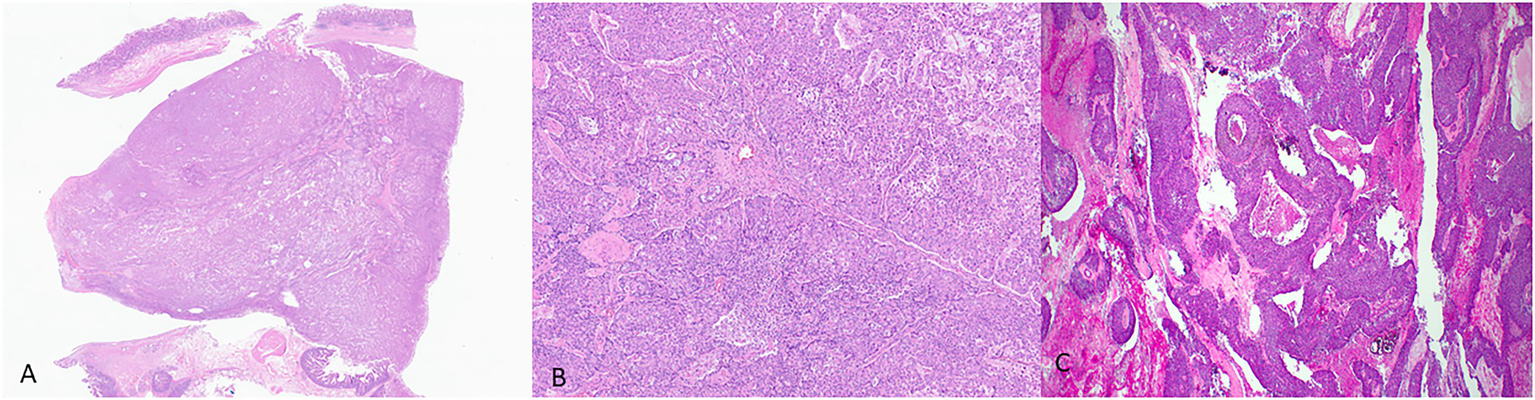

In IOPNs, the neoplastic epithelium forms complex, thick papillae with intraepithelial and intracellular lumina (Figure 2). The neoplastic cells contain abundant eosinophilic cytoplasm, and the nuclei are round with prominent nucleoli. IOPNs almost always have high-grade dysplasia and are associated with invasive carcinoma in about 30% of the cases (WHO Classification of Tumours Editorial Board, 2019). Rarely, the invasive component may show abundant mucin accumulation (Wang et al., 2019). IOPNs with a predominantly solid pattern can resemble acinar cell carcinoma or pancreatic neuroendocrine neoplasms. Immunohistochemistry for BCL-10, trypsin, and neuroendocrine markers is essential in this differential diagnosis.

Figure 2

Representative histological pictures of intraductal oncocytic papillary neoplasm (IOPN). (A) Low magnification shows intraductal papillary proliferation. (B) Intermediate magnification shows the thick, complex papillae. (C) Higher magnification shows that the neoplastic cells have abundant and distinctly oncocytic (eosinophilic) cytoplasm. The nuclei are round and often contain prominent nucleoli. (A) Original magnification 10×. (B) Original magnification 100×. (C) Original magnification 200×.